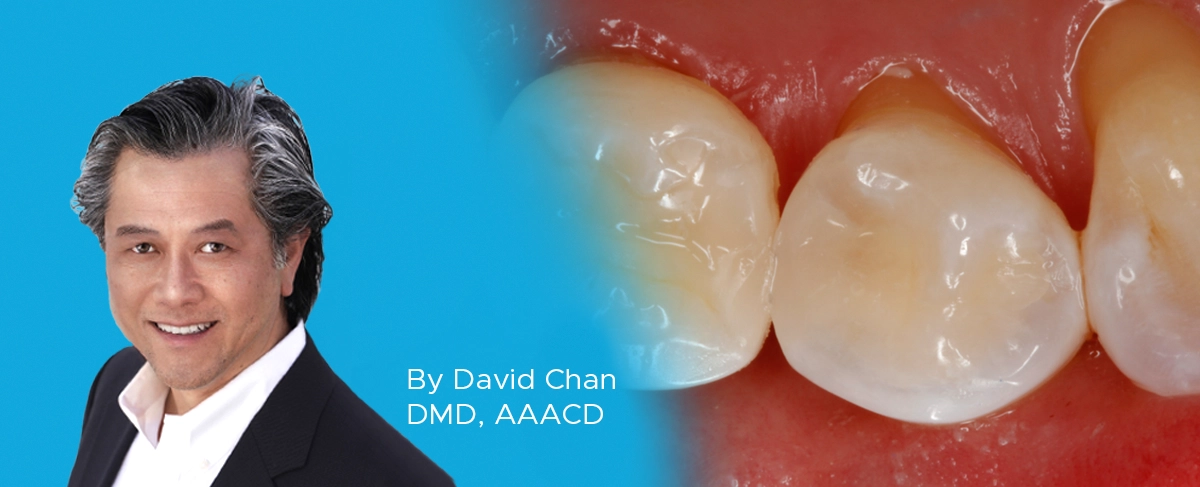

A young female physician presented to my office with a chief complaint of sensitivity to cold and sweets in her lower right dentition which has been persistent for approximately 1 month. Upon clinical and radiographic examination, it was determined that her lower right first premolar #28 (#44) had a previous restoration that had fractured and was compromised by recurrent caries. (FIG. 1)

The carious lesion was rather deep into the tooth according to the radiographic image but not wide. The carious lesion was less than ½ the distance between the buccal/lingual cusp distance making this an excellent case for a direct composite restoration. (FIG. 2)

Tooth #28 (#44) was diagnosed with a fractured DO composite restoration with recurrent caries and a mesial fossa with caries. It was determined that a minimally invasive restoration, using a direct composite DO and a separate occlusal restoration in the mesial fossa were required.

A DO preparation and a separate occlusal preparation were made in tooth #28 (#44). Due to the depth of the caries in close proximity to the pulp, only the infected dentin was removed, as leaving the affected dentin in place aligns with minimally invasive dentistry. Numerous peer reviewed studies have shown the affected dentin will re-mineralize over time on its own.¹ (FIG. 4)

A DO preparation and occlusal preparation was made in tooth #28 (#44). Only the infected dentin was removed.